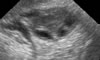

1-Yumurtalık, içerisinde, yumurta hücrelerini bulunduran, dişi organ kısmıdır.

2-Dişi eşey organı, yumurtalık.

3-Yumurtalık, yumurtaların meydana geldiği yer.